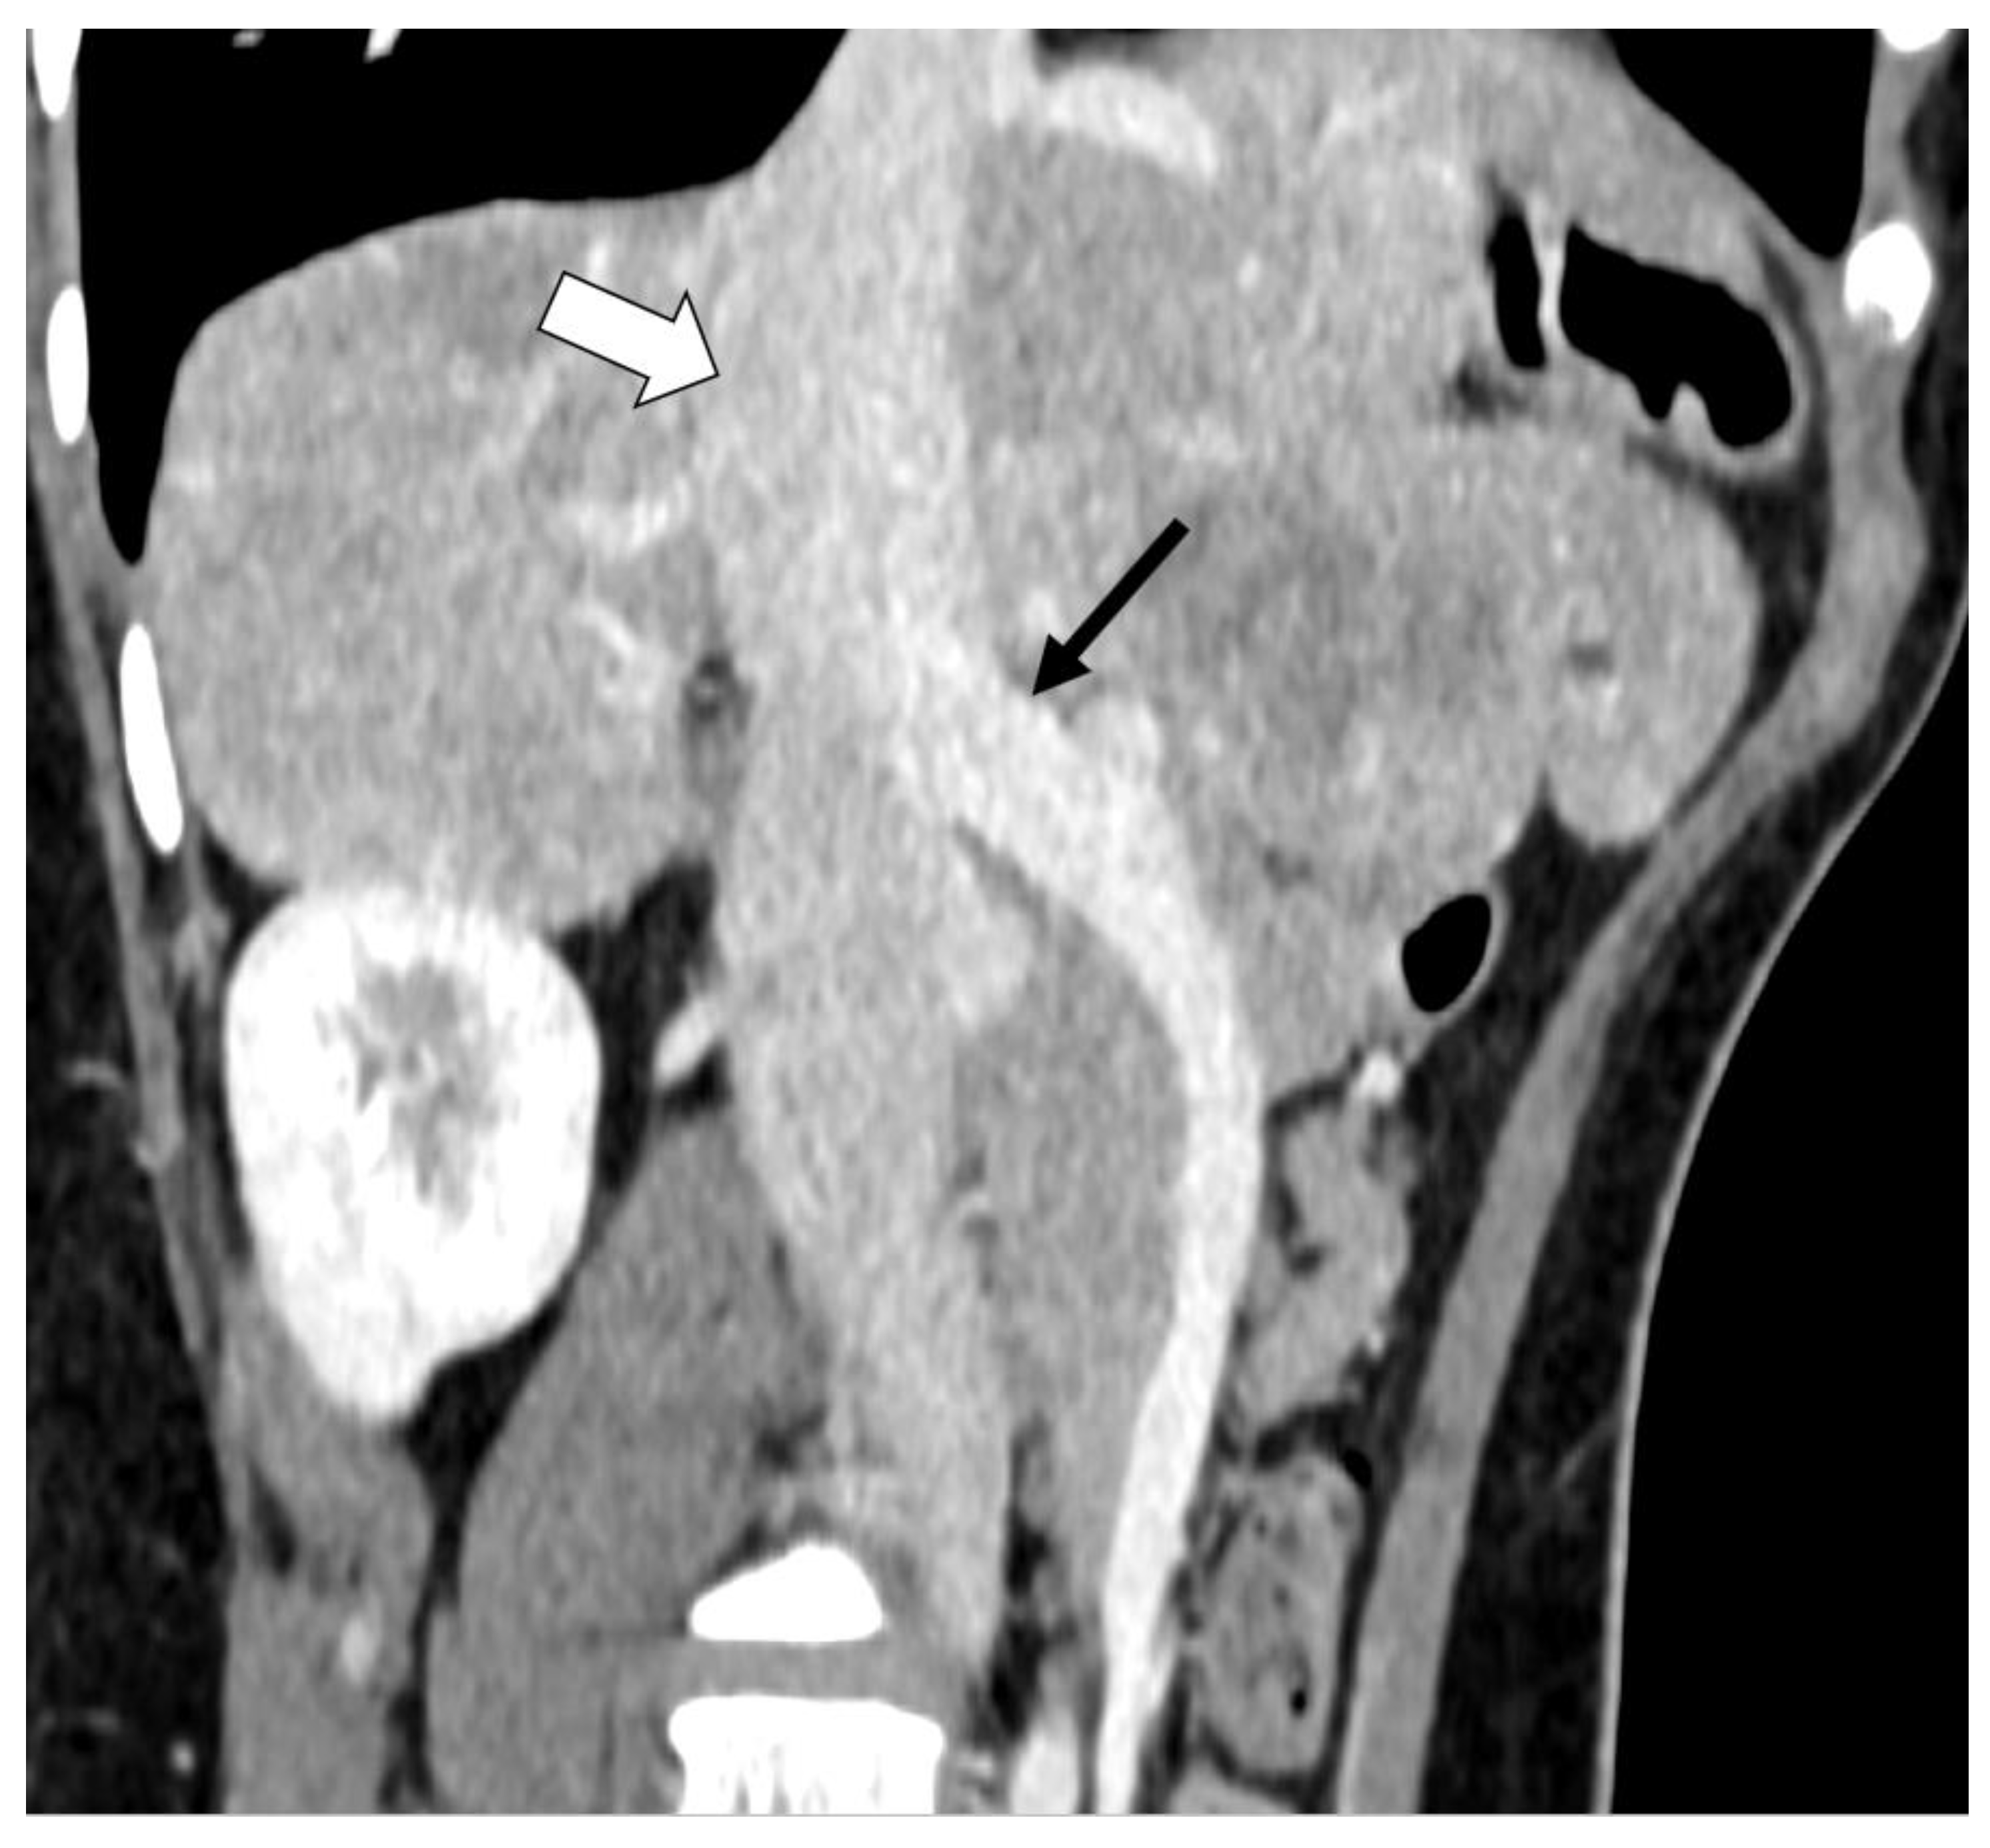

2.4. Case D (Dog)

2.5. Case E (Cat)